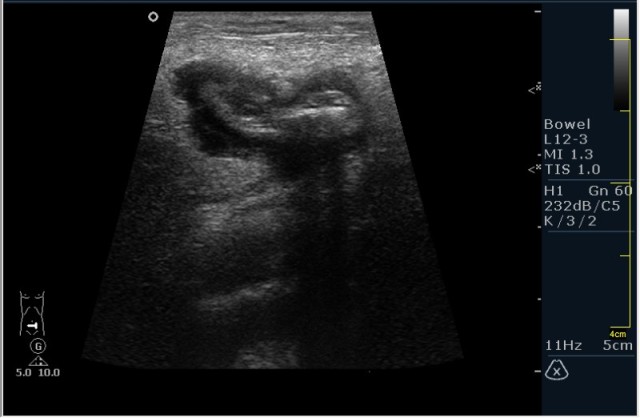

Пациент М. 60 лет с болями в левой подвздошной области. Пациент был направлен на УЗИ с диагнозом: левосторонняя почечная колика. Жалобы на боли в левой подвздошной области отдающие в таз. Анамнез без особонностей.

Пациента я сразу направил на эндоскопию. К сожалению, заключение было ожидаемым с моей стороны, опухоль (карцинома по результату биопсии).